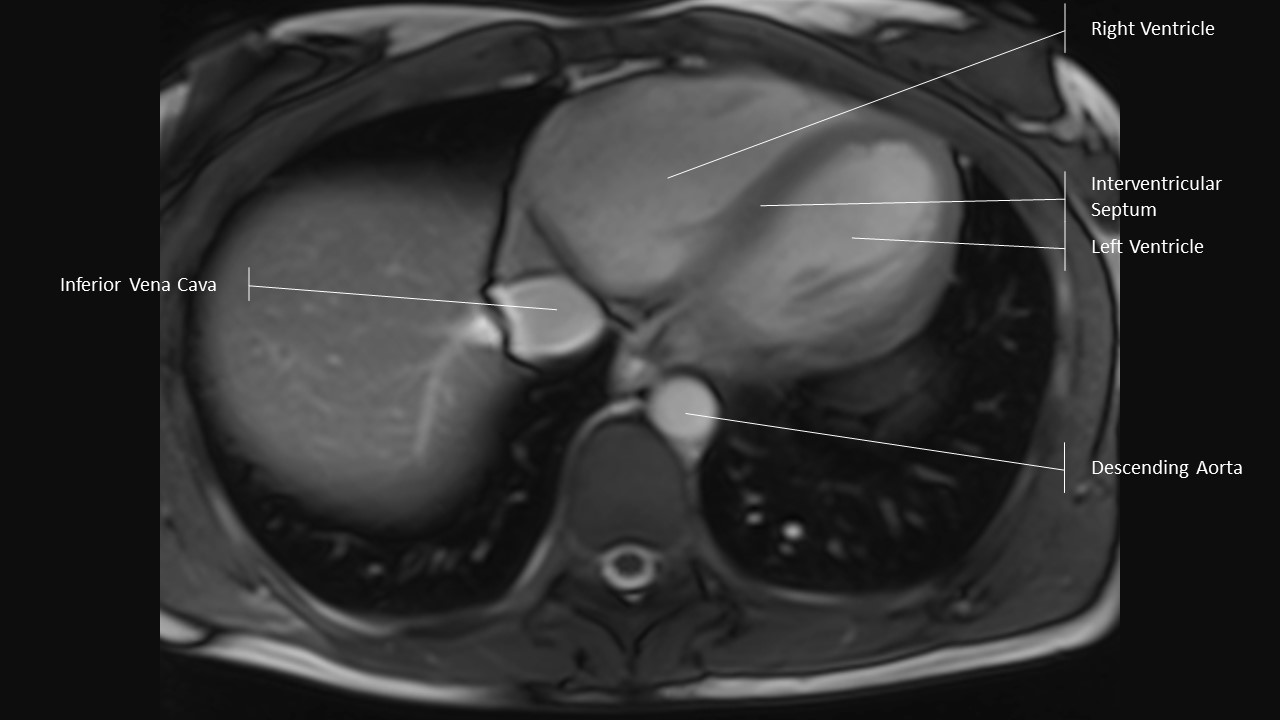

Axial Series